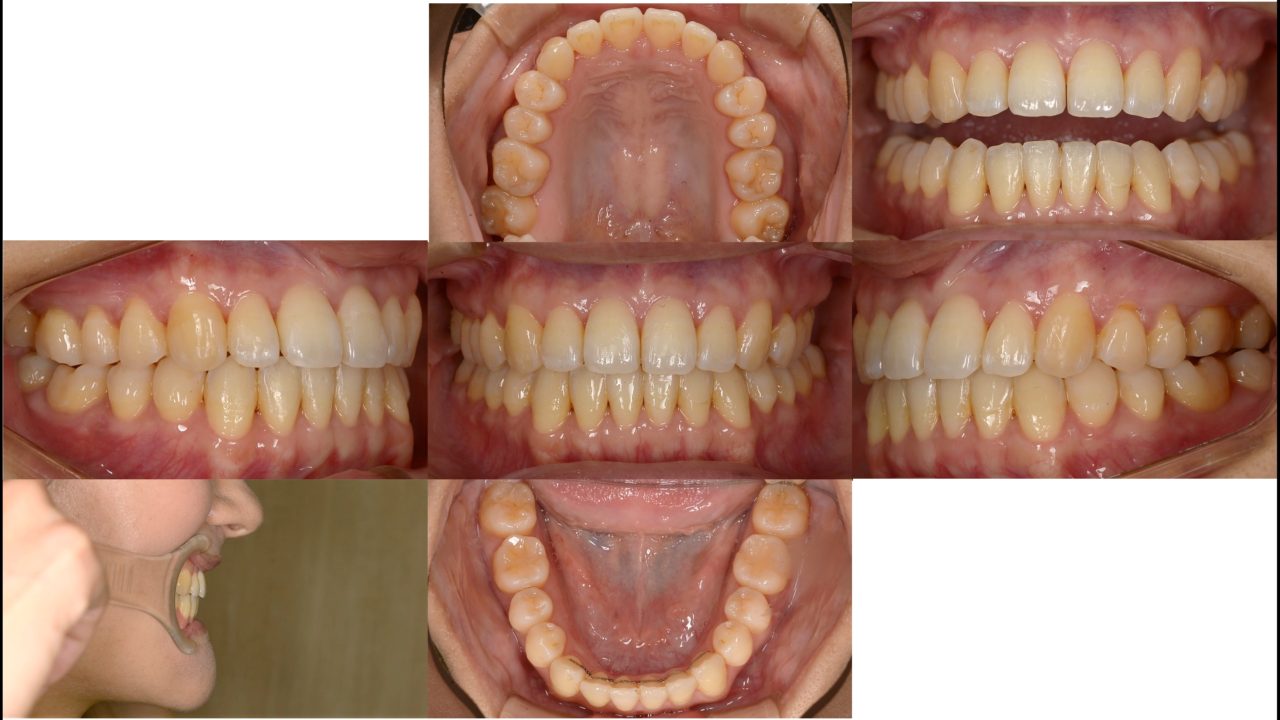

矯正治療終了 2021.4.24

動的治療期間は22か月でした。予定より時間はかかりましたが、口元が大きく引っ込み、非常にきれいなスマイルになりました。歯を抜かずにこの結果を得られたことは非常に価値があります。